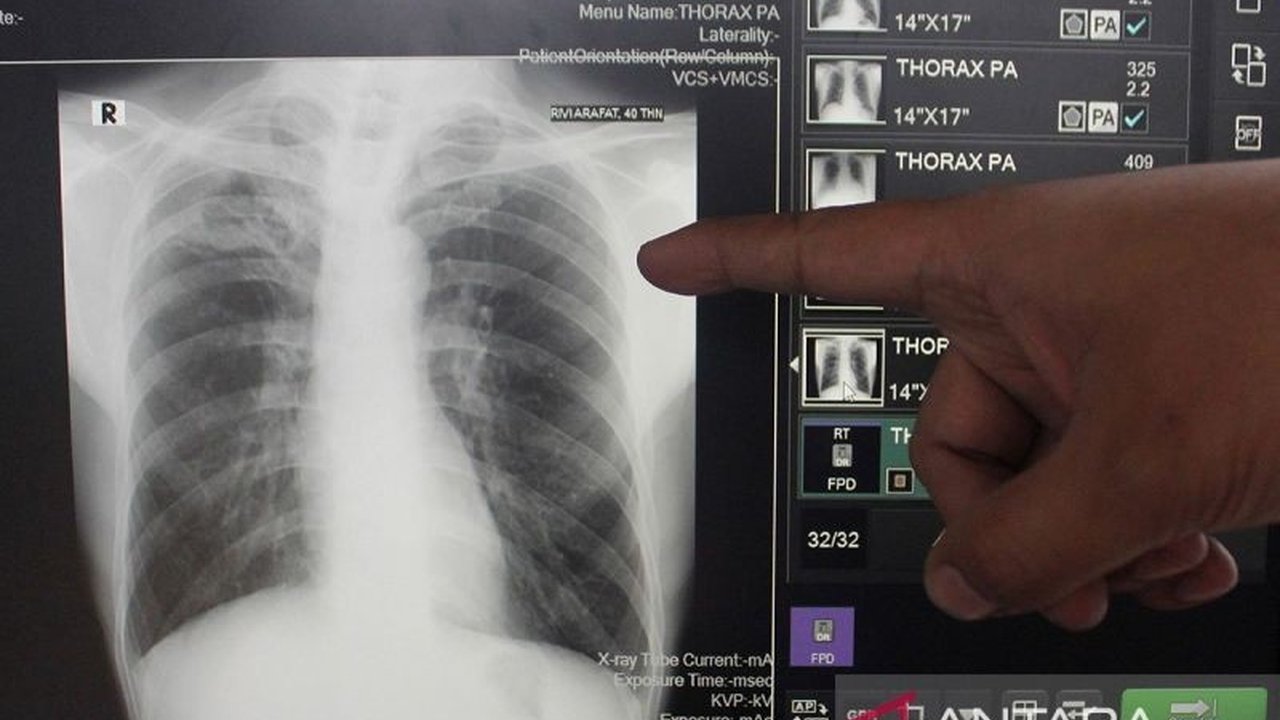

Kementerian Kesehatan (Kemenkes) RI baru saja merilis data terbaru mengenai kasus tuberkulosis (TBC) di Indonesia. Berdasarkan laporan Plt. Dirjen Penanggulangan Penyakit Kemenkes, Murti Utami, tercatat sebanyak 856.420 kasus TBC telah ternotifikasi hingga tahun 2024. Angka ini mendekati target absolut yang ditetapkan sebesar 900 ribu kasus, menunjukkan upaya signifikan dalam deteksi penyakit menular mematikan ini.

Dari total 856.420 kasus TBC yang ternotifikasi, sebanyak 844.292 kasus merupakan TBC Sensitif Obat (SO), mencapai 98,6 persen dari total kasus. Sementara itu, kasus TBC Resisten Obat (RO) tercatat sebanyak 12.128 kasus. Untuk pengobatan, sebanyak 779.193 pasien TBC SO telah menerima pengobatan (treatment enrollment), mencapai 92 persen dari target. Sedangkan untuk TBC RO, sebanyak 9.573 pasien telah menerima pengobatan, atau 79 persen dari target 90 persen.

Tingkat keberhasilan pengobatan (treatment success rate) juga dilaporkan. Untuk TBC SO, angka keberhasilan mencapai 85 persen dari target 90 persen, sementara untuk TBC RO, angka keberhasilan mencapai 59 persen dari target 80 persen. Meskipun angka keberhasilan pengobatan TBC SO cukup tinggi, masih terdapat ruang untuk peningkatan, terutama pada kasus TBC RO yang tingkat keberhasilannya masih di bawah target.

Salah satu tantangan yang dihadapi adalah pemberian pengobatan untuk terduga TBC (Terapi Pengobatan TBC). Hingga saat ini, baru 19,4 persen (79.008 pasien) dari target 50 persen yang telah menerima pengobatan. Hal ini menunjukkan perlunya peningkatan upaya screening dan deteksi dini kasus TBC untuk mencapai target yang telah ditetapkan.